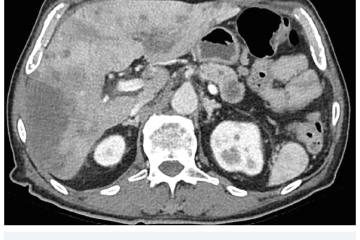

Několik studií se zabývalo AI asistovanou CT detekcí karcinomu pankreatu s AUC 0,79–0,99 %,6–8 tedy přesností porovnatelnou s přesností práce zkušeného radiologa. Stran časné detekce proběhla studie posuzující přesnost AI modelu v detekci karcinomu pankreatu v období 3–36 měsíců před prvními projevy onemocnění. Zařazeno bylo 155 pacientů s karcinomem pankreatu a 265 zdravých kontrol. AI model zde dosáhl AUC 0,98, což výrazně předčilo radiology, kteří při popisování stejných případů dosáhli AUC 0,66.9 Studie využívající DL model pro rozlišení zdravé slinivky od nálezu pankreatických neoplazií, tedy karcinomu pankreatu, intraduktální papilární mucinózní neoplazie (IPMN), serózních a mucinózních cystických neoplazií a solidní pseudopapilární neoplazie, byla prezentována s AUC 0,91, tedy opět odpovídající přesnosti popisu radiologa.10 Pro další vývoj a možné klinické využití bude potřeba přístupu k rozsáhlému archivu CT snímků karcinomu pankreatu, aby se ML modely mohly zdokonalovat. Další studie se věnovaly AI asistované diferenciální diagnostice. Ta bývá u lézí pankreatu velmi obtížná a pokrok v této problematice je tak velmi přínosný. Mezi nejzajímavější patří studie zabývající se rozlišením serózních a mucinózních cystadenomů s AUC 0,932.11 Další studie zkoumala úspěšnost rozlišení karcinomu pankreatu od zbytnění pankreatu při určitých formách chronické pankreatitidy (MFP – mass forming pancreatitis) s AUC 0,866.12 V další studii byla AI využita k rozlišení fokální autoimunitní pankreatitidy od karcinomu pankreatu s AUC 0,97.13 V rámci MR proběhlo několik studií, které se zaměřily na AI asistované zachycení a klasifikaci pankreatického karcinomu či IPMN. Studie klasifikující IPMN pomocí konvoluční neuronové sítě (CNN – convolutional neural network) byla schopna rozlišit dysplazii vysokého stupně od přítomnosti karcinomu se senzitivitou 76 %, specificitou 78 % a AUC 0,78.14 Další studie porovnávala AI modely CT a MR v predikci maligního IPMN. Výsledky ukázaly, že MR model s AUC 0,94 byl přesnější než CT model s AUC 0,864.15 S využitím PET/CT byl prozkoumán AI model rozlišující od sebe akutní pankreatitidu a karcinom pankreatu s AUC 0,9668.16 Výsledky AI v oblastech zobrazovacích metod jsou tak slibné. Dosahují minimálně přesnosti srovnatelné s radiologem a zejména v problematice časných karcinomů pankreatu člověka svojí přesností převyšují (obr. 1–5).